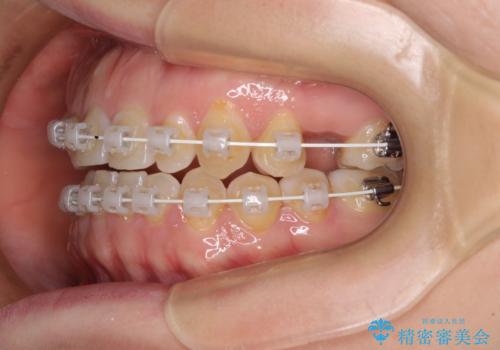

隙間の空いた歯列とボロボロの乳歯 インプラント治療と矯正治療

歯列はワイヤー矯正にて改善することとしましたが、上下歯列にも隙間があったので、舌の突出癖を改善するトレーニングを徹底的に行うこととしました。

舌の突出癖改善のトレーニングが全くうまくできず、治療期間が長期化しました。

早く治療を終えたいとの要望があり、トレーニング次第と伝えるとようやく練習をするようになり、その後は速やかに上下の隙間が改善されました。